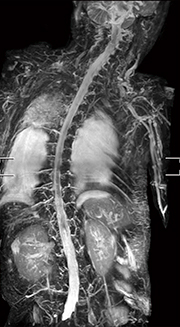

さらに,高画質化と撮像時間の短縮化が図られたことが,多くの臨床的な有用性をもたらしている。その中でも,高橋医長は全身body DWIを高く評価している。

「Ingenia 3.0Tでも全身body DWIを施行していたのですが,3T特有のSARの増大により,どうしても1.5T装置と比較すると,検査時間がかかってしまうため,あまり積極的に撮像していませんでした。それが,Prodiva 1.5T CXでは,SARによる撮像時間の延長がなく,コイルの軽量化により,セッティングも非常に簡便です。さらに,SNRが高くゆがみも少ないために,高画質な画像が短時間に得られるようになりました。従来30分以上かかっていた頭部から鼠径部までの全身body DWIが,撮像時間8〜9分,トータルの検査時間18分程度で可能となり,大幅な時間短縮を図れています」

症例2:悪性黒色腫

稼働間もない時点ですでに,3T装置と遜色ないパフォーマンスを発揮し,多くのメリットをもたらしているProdiva 1.5T CXであるが,聖隷三方原病院では,今後その能力を十分に生かせるよう,検査枠などの見直しなども検討している。高橋医長は,「セッティングを含めた検査スループットが良いので,骨転移症例の探索などに全身body DWIを積極的に使用できます。全身body DWIは,血液内科をはじめ,悪性腫瘍を扱う診療科の医師からも有用性が認められており,今後は検査枠を設けて施行していくことを検討しています」と述べる。高橋医長は,例えば悪性リンパ腫において,まずFDG-PET検査できちんと診断した上で,フォローアップを全身body DWIでも行うことで,その後のFDG-PET検査を減らすことも可能になると考えている。心臓MRIについても,現時点でもまったく問題なく撮像できているが,今後のバージョンアップでT1マッピングが可能となる予定で,よりいっそう有用な検査になることに期待している。